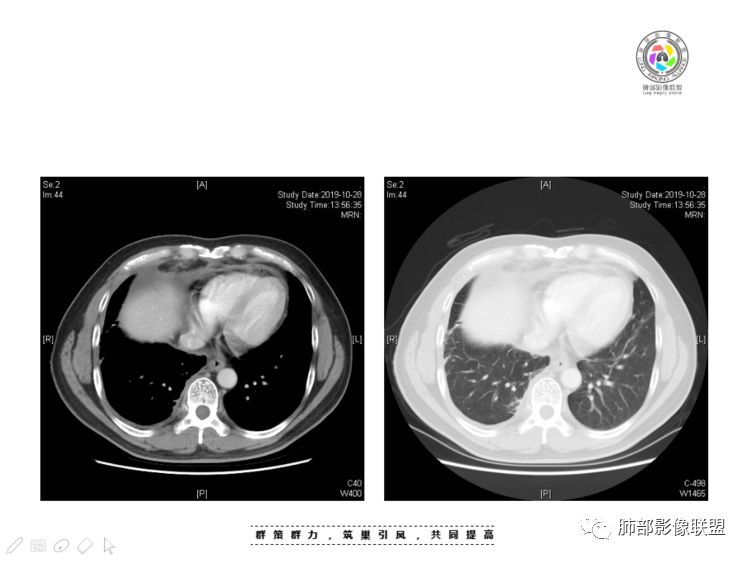

本例纵隔与肺内两处病变,回顾总结分析:

1、右肺内病灶,病灶呈结节样,边缘欠规则,局部膨隆,叶间裂胸膜牵拉凹陷,再看相应支气管腔堵塞截断,临床资料胸水中查到癌细胞,均提示病灶倾向恶性,腺癌的病理意见与之相吻合。

2、前纵隔内病灶囊实性混杂密度病灶,囊性病灶主要位于右侧,张力较高,有分隔影,囊壁右侧缘光整,病灶左侧实性部分边界不清明显强化,病灶肺瘤交界面大部分边界清楚,部分模糊。

胸腺瘤/胸腺癌:病灶内那么大的囊,常规考虑B型以上胸腺瘤,囊内有分隔影,病灶周围脂肪间隙模糊,常规考虑侵袭性胸腺瘤或胸腺癌,若侵袭性胸腺瘤,常侵犯胸膜、心包,很少累及肺。胸腺癌易侵犯胸膜、肺并纵隔淋巴结及远处转移。但肺内腺癌形态更符合原发灶。胸膜及叶间裂转移则即可来自肺,也可来自胸腺癌。